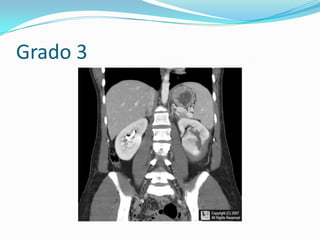

Grado 3: Laceración renal sin extravasación

Grado 3:laceración sin extravasación

Grado 3

Grado 3: Laceraciónrenal sin extravasación